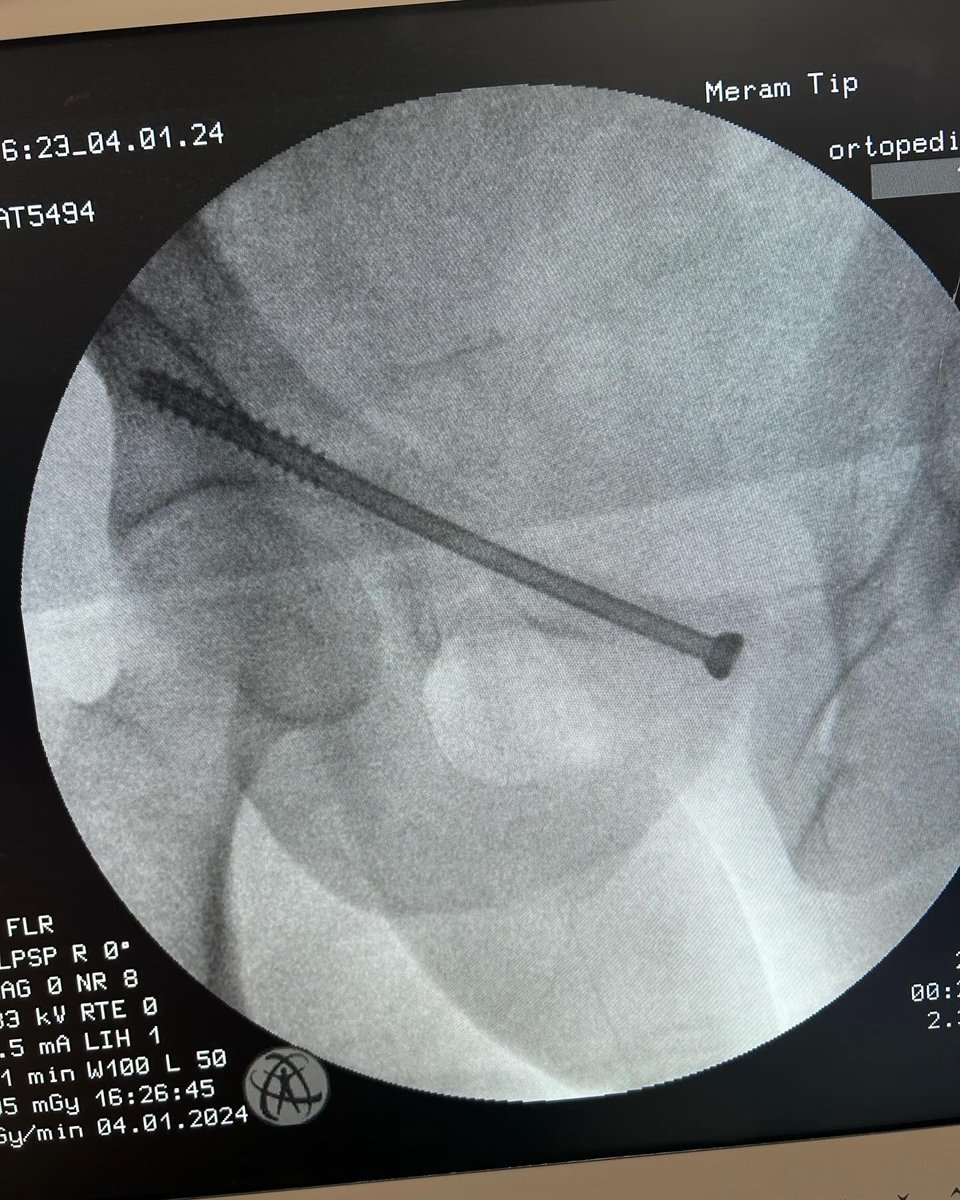

Male 40yo, healthy and physically active.

How do you treat this fracture?

Nonop, ORIF with plate or nailing?

@InvictaOrtho @traumaticum @rkh_md @Gnomelover1970 @aqueipot @DrMarecek

@DrBhavinJadav

#orthotwitter